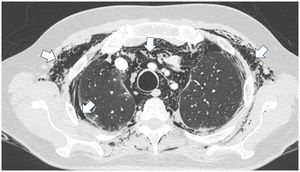

Presentación de casosCaso 1Mujer de 60 años con antecedente de DM con anticuerpos anti-MDA5 positivos diagnosticado un año atrás y quien en el momento del diagnóstico presentó afección cutánea dada por eritema en heliotropo, signo del chal, signo de Gottron y lesiones violáceas y ulceradas en palmas, poliartritis, debilidad proximal de las 4 extremidades y cefaloparesia. Al inicio se le prescribió metotrexato 20mg semanal y prednisolona 20mg diarios con esquema de desmonte. A los 3 meses de seguimiento persistía con lesiones cutáneas, debilidad muscular y elevación marcada de enzimas musculares, y adicionalmente alopecia, por lo cual se consideró que había, además de refractariedad clínica, un posible efecto adverso del metotrexato, decidiéndose iniciar primer ciclo de rituximab 1g IV días 0 y 15, más azatioprina 100mg diarios. Consulta luego de 2 meses por persistencia de las lesiones en la piel y poliartritis, a pesar de mejoría de la debilidad muscular y normalización de enzimas musculares. En el examen físico se encontró tumefacción de articulaciones: interfalángicas proximales, metacarpofalángicas, carpos y codos, adicionalmente con eritema en heliotropo, pápulas de Gottron, máculas y placas eritematoso-violáceas con incipientes signos de ulceración (fig. 1). También se encontraron crépitos en ambos campos pulmonares, por lo cual se solicitó TAC de alta resolución, la cual demostró neumomediastino extenso aislado sin presencia de neumotórax ni enfisema cutáneo (fig. 2). Se descartó perforación esofágica mediante endoscopia digestiva superior y lesión bronquial por broncoscopia, por lo cual se atribuyó este hallazgo a manifestación propia de la DM, en ausencia de EPI. Ante la estabilidad clínica y la ausencia de síntomas respiratorios, se inició ciclofosfamida 500mg IV mensuales durante 6 meses. Actualmente se encuentra en seguimiento por la consulta externa a la espera de completar el esquema propuesto, clínicamente con mejoría de las lesiones en la piel y de la disnea.